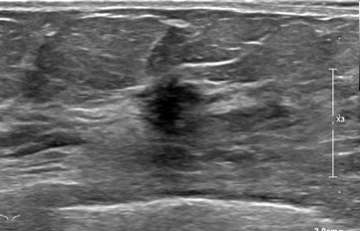

Case: Invasive Lobular Carcinoma Figure 3

MRI evaluation revealed an irregular mass at 9 o’clock with relatively fast washout on kinetics. No further disease was identified on MRI.